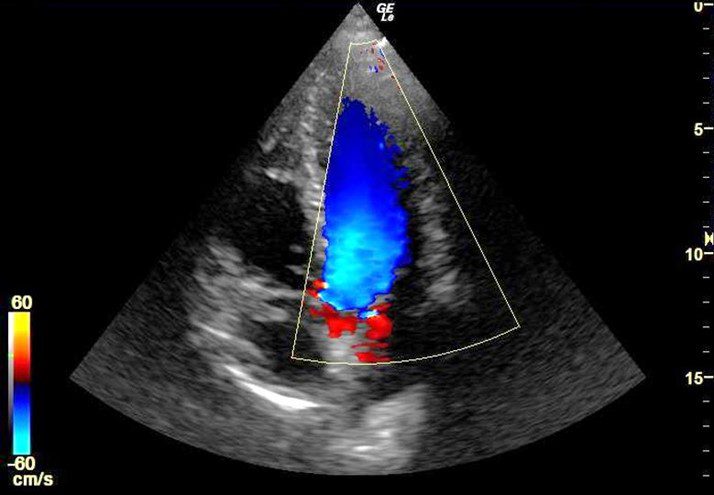

联合国难民署-心脏彩色多普勒超声仪-叙利亚

RFQ/HCR/SYR/24/71

2024-11-20